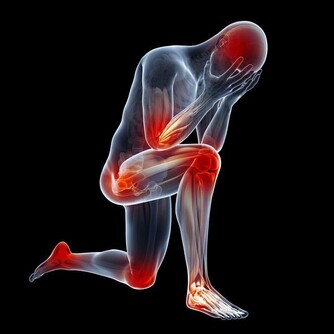

中醫講:“腎主骨,骨升髓”,生氣多時會導致骨痛,肢體麻木,關節炎等。